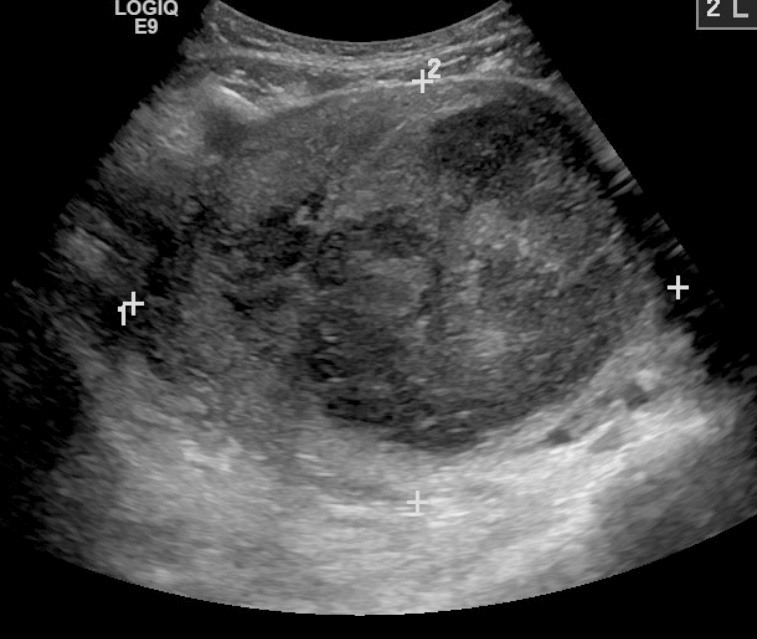

Leiomyomas, also known as fibroids, are benign and often asymptomatic neoplasms of the myometrium. Incidence peaks in the fifth decade of life. There appears to be a strong genetic component, with obesity as a noted risk factor.6 Other risk factors include Black race, lack of physical activity, smoking, alcohol and caffeine consumption, and nulliparity.24 Although the majority of patients with fibroids are asymptomatic, patients may experience urinary symptoms, congestion, dyspareunia, and constipation in addition to HMB and AUB.6 The size of the leiomyoma appears to have a direct effect on the degree of bleeding.11 Medical management of symptomatic leiomyomas includes gonadotropin-releasing hormone (GnRH) agonists, such as leuprolide acetate, which remains the gold standard for improving both symptoms and reducing leiomyoma burden in patients.25 Other therapies include NSAIDs, LNG-IUD, and surgical interventions ranging from uterine artery embolization to myomectomy and hysterectomy.24 (See Figure 1.)

Figure 1. Transvaginal Ultrasound Demonstrating a Leiomyoma |

![]() |

Source: James Heilman, MD, CC BY-SA 3.0 https://creativecommons.org/licenses/by-sa/3.0, via Wikimedia Commons |